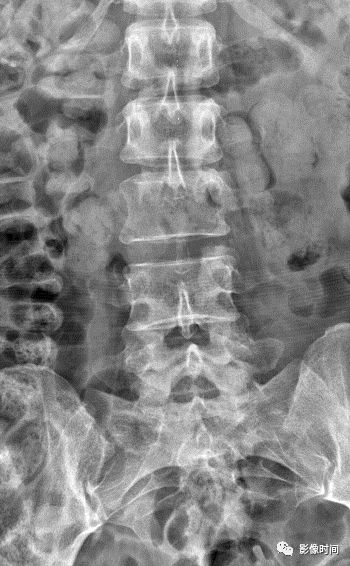

19竹节椎

竹节椎(Bamboo spine)

竹节椎是用于描述强直性脊柱炎的一个放射学特征,由于椎旁韧带广泛骨化,导致椎体融合强直,这种薄而连续的韧带骨化在正位片使得脊柱的轮廓呈现波浪起伏状,宛如具有多个竹节的一根竹竿,故而得名。

典型病例

强直性脊柱炎。腰椎正位片示腰椎韧带、小关节囊广泛骨化,骨性强直,呈典型竹节椎表现。另可见骶髂关节骨性融合。

引用自:https://radiopaedia.org/ articles/ bamboo-spine-ankylosing-spondylitis